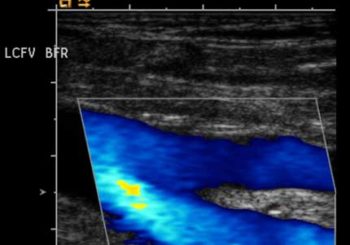

Arteriyel Doppler Ultrason Doppler Ultrasonografi, özellikli ultrason cihazları ile ve konusunda uzman radyologlar tarafından uygulanan bir yöntemdir. Arteriyel Doppler Ultrason ve Venöz Renkli Doppler Ultrason olarak değerlendirmeler yapılabilir. Bu yöntem ile bir damardaki veya bir organdaki kan akımı incelenebilir, kan akımının yönü,damarda daralma olup olmadığı, akan kan miktarı değerlendirilir. Tüm bu değerlendirmeler real time yapılır, yani o anda değerlendirme yapılır, tetkik sonucu he...

Venöz Doppler önemlidir